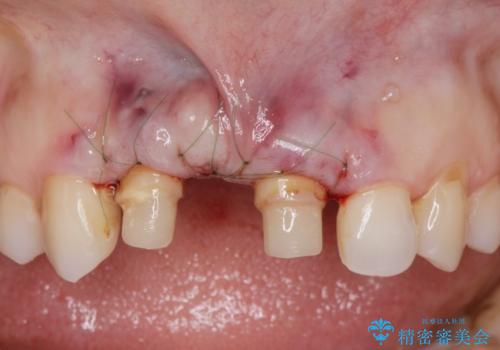

根管治療を行ったのち、歯周外科を行うことで、欠損部の歯ぐきの厚みを出し、縁上歯質を獲得することで、長期的な予後の見込めるブリッジを製作できる環境を整備していきます。

歯周外科をおこなったことで歯ぐきのラインを整え、脱離しないような前歯のブリッジを作製することができました。